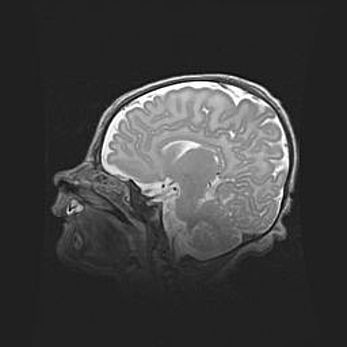

Церебральная ишемия II.

Возраст: 5 дней

Вес: 3400 г

Пол: женский

Окружность головы: 35 см

Срок гестации: 39 недель

Церебральная ишемия – это заболевание, характеризующееся недостаточностью (гипоксией) либо полным прекращением (аноксией) снабжения мозга кислородом по причине закупорки одного или нескольких сосудов. Это приводит к  что метаболическим расстройствам различной степени тяжести в тканях головного мозга, развитию коагуляционных некрозов и гибели нейронов.